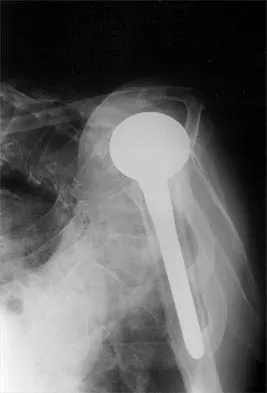

A 72-year-old woman who was doing well after undergoing total shoulder arthroplasty for arthritis 4 months ago is suddenly unable to elevate her arm. Examination reveals 70 degrees of external rotation compared with 45 degrees on the uninvolved side, and she is unable to lift her hand off her lower back. Radiographs are shown in Figures 43a through 43c. Treatment should consist of

Explanation

Results of treatment of subscapularis rupture are best when immediate repair is performed. When the cause of the anterior instability is the result of rupture of the subscapularis tendon and the component position is acceptable, revising the position of the component is unnecessary. Restoring the coracoacromial arch and subacromial decompression are related to superior instability and rotator cuff pathology, respectively, and would not correct the instability caused by subscapularis rupture. Moeckel BH, Altchek DW, Warren RF, Wickiewicz TL, Dines DM: Instability of the shoulder after arthroplasty. J Bone Joint Surg Am 1993;75:492-497.